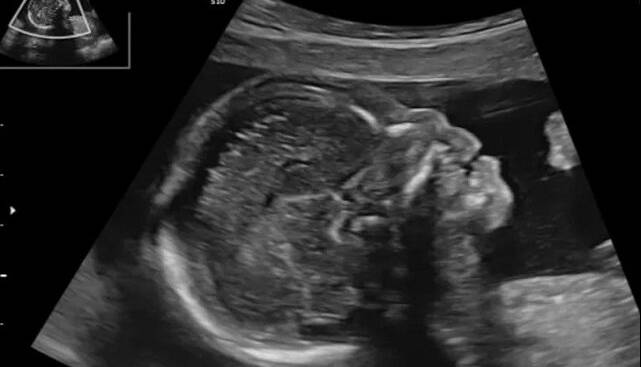

ایسنا/در سالهای اخیر پیشرفتهای تصویربرداری در بارداری به پزشکان امکان داده تا زودتر از گذشته ناهنجاریهای جنینی را تشخیص دهند. یکی از شاخصهایی که در این مسیر اهمیت زیادی یافته، وضعیت استخوان بینی جنین است که میتواند نشانهای از برخی اختلالات ژنتیکی باشد.

در ایران نیز با توجه به تنوع قومی و ویژگیهای ژنتیکی گوناگون، اندازه و رشد استخوان بینی ممکن است با میانگینهای جهانی تفاوت داشته باشد. به همین دلیل بررسی وضعیت این استخوان در جنینهای ایرانی در سهماهههای مختلف بارداری میتواند به بهبود غربالگری و کاهش نتایج اشتباه در تشخیص کمک کند. اهمیت این بررسی زمانی دوچندان میشود که بدانیم سونوگرافی یکی از کمخطرترین و در دسترسترین ابزارهای بررسی سلامت جنین است.

در این پژوهش، ۲۶۵ خانم باردار مراجعهکننده به کلینیک پریناتولوژی دانشگاه علوم پزشکی سبزوار مورد بررسی قرار گرفتند. در این مطالعه، جنینهایی که در سونوگرافی سهماهه اول استخوان بینی آنها مشاهده نمیشد یا در سهماهه دوم دچار کوتاهی غیرطبیعی این استخوان بودند، وارد تحقیق شدند. دادههای استخراجشده از پرونده بیماران با استفاده از نرمافزار آماری مخصوص تحلیل شد تا ارتباط میان اندازه استخوان بینی و نتایج ژنتیکی مشخص شود.